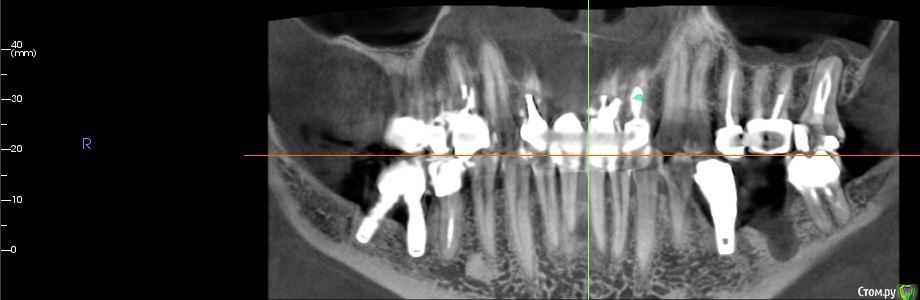

Мне 52 года, не курю. Сейчас имеет подвижность и "на честном слове" держится единая конструкция на передних  верхних. Около 27  в сторону 8 периодически образуется гнойный свищ (была литая вкладка, ее прошел врач, заложил лекарство полгода назад, гной прорывается реже).

14 имеет неощутимую мной подвижность (хирург сказал). 35-имплант, был в паре под единой коронкой с 36 (оба 2006 года). 3 мес. назад 36 дезинтегрировался, коронку распилили, не беспокоит. 43.43 имеют наружные прикорневые пломбы. 46-имплант 2009 года, конструкция на месте очень длительно отсутствующего зуба, специально задумана под углом и открыта для ежедневного ухода, тоже не беспокоит. Зубной ряд был идеально полностью восстановлен в 2010 году. После были удаления 18, 28, 47.   Заранее благодарна за все профессиональные советы.